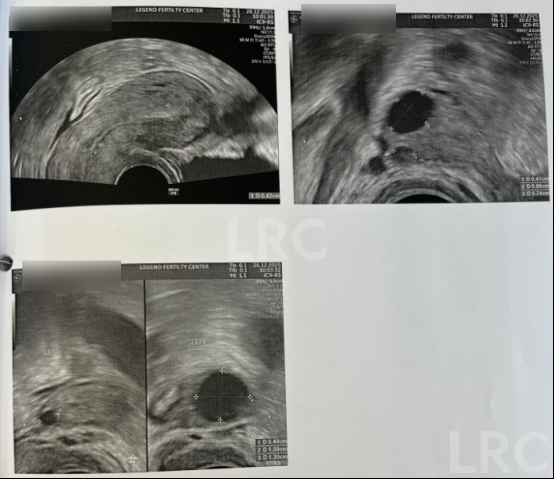

月经第二天 促排第一天

阴超检查:基础卵泡 2 颗

- 右侧卵泡 1 颗 (6mm)

- 左侧卵泡 1 颗 (7.5mm)

促排第三天

阴超检查:

- 右侧卵泡 2 颗 (9,4mm)

- 左侧卵泡 2 颗 (11,5mm)

促排第六天

- 右侧卵泡 2 颗 (13,9mm)

- 左侧卵泡 2 颗 (17,7mm)

促排第十天

- 右侧卵泡 2 颗 (20,15mm)

- 左侧卵泡 2 颗 (23,7mm)